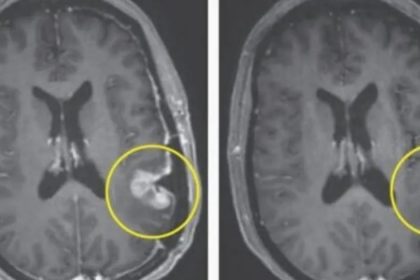

Brain Cancer Treatment Shows Promise As Tumor Almost Disseapers in 5 Days : The Hearty Soul

A new brain cancer treatment has demonstrated incredible promise as a brain…